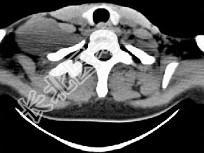

- 单项选择题女,47岁, 下颈部触及一包块约五年余,CT如图所示, 最可能诊断为  (    )

- A、滑膜肉瘤

- B、血管瘤

- C、神经鞘瘤

- D、副神经节瘤

- E、巨淋巴结增生症